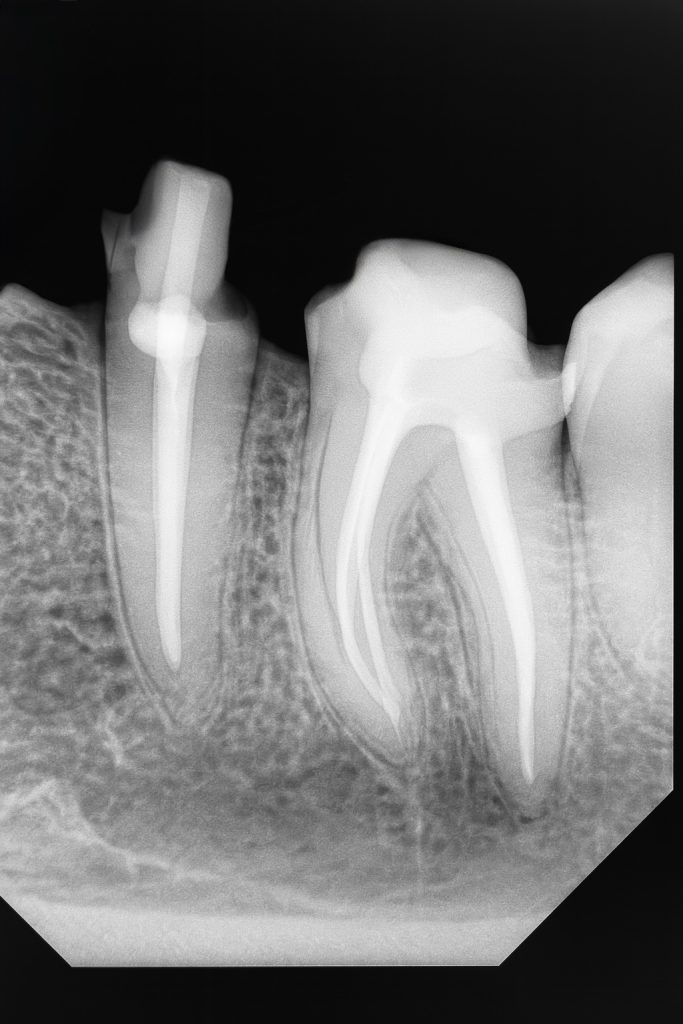

The patient presented with a grossly decayed mandibular premolar (Fig 1). Clinical and radiographic evaluation revealed pulpal necrosis and compromised coronal walls but sufficient root length for retention.

- Fig 1: Pre-operative view showing extensive coronal destruction.